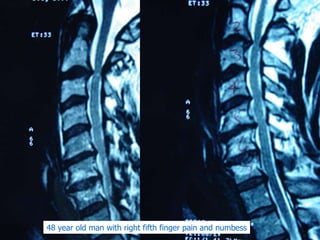

48 year old man with right fifth finger pain and numbess

48 year oldman with right fifth finger pain and numbess